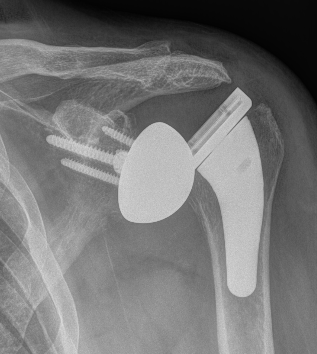

Instability / Dislocation

Dislocated Reverse TSRDislocated Reverse TSR Lateral

disdis

Early dislocation issues

Soft tissue tension  Axillary nerve palsy Component position  Component size

Humeral distalization

- increased liners

- longer humeral body

Inferior base plate  / inferior impingement

Increased glenosphere size increases jump distance

Glenoid lateralization

- lateralized glenosphere

Subscapularis

Late dislocation

Liner wear

Heterotopic ossification

Revision

Melbourne et al JSES 2023

- revision for instability in 36 rTSA

- glenoid sided revision: 66% successful

- humeral sided revision: 66% successful

- bipolar revision: 90% successful